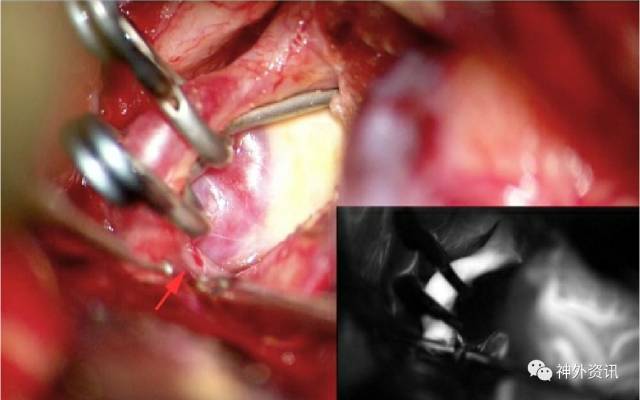

图20:,使用一个直角开窗动脉瘤夹夹闭小的向后突出的PCoA动脉瘤 (上方手绘图)。开窗夹环绕着ICA。可见AChA位于动脉瘤夹远端,ICA分叉的近端。利用这种方法,即使AChA(箭头)粘附在大的动脉瘤顶,也无需游离AChA(中下照片。)

夹闭向内侧突出的动脉瘤时,动脉瘤夹叶片远端可能被后床突挡住,无法获得最佳夹闭位置。在这种情况下成角开窗动脉瘤夹特别有用。除非证明有其他原因,否则运动诱发电位的丧失很可能是AChA/PChA及其穿支被损伤的标志。